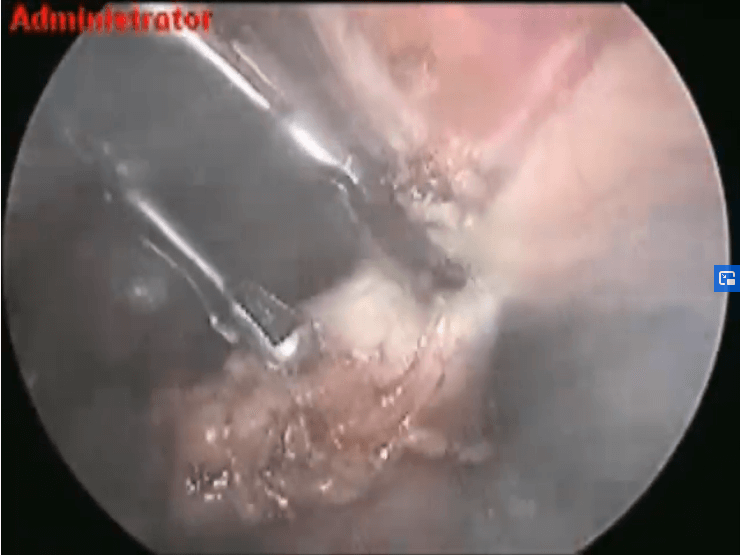

Laparoscopic Adhesiolysis and Ovarian Cystectomy